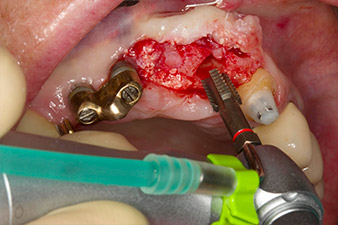

Después de la cicatrización primaria, los tejidos blandos se modelaron con ayuda del puente con base reconstruida. Dos meses después, se procedió a la exposición del área con una incisión de la cresta maxilar en sentido ligeramente palatino (figura 2).

El hueso alveolar de la posición 22 resultó tener unas dimensiones suficientes. Las figuras 2 y 4 muestran la preparación del lecho del implante, el corte de rosca y la colocación del implante con el equipo Implantmed.